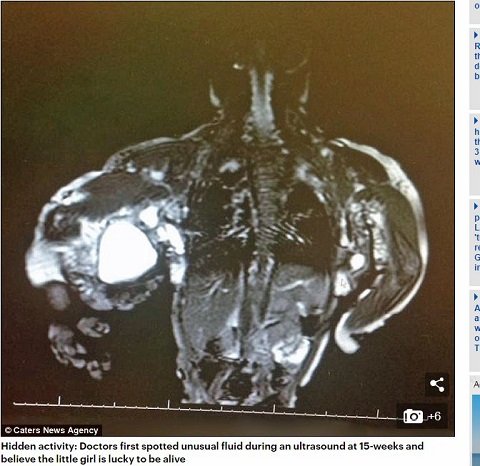

数カ月にも及ぶ検診の後、マディソンが「CLOVES(クローヴス)症候群」と診断されたのは生後3カ月のときだった。これは非常に稀な症候群で、現在までわずか200人の患者しか確認されていない。一説によると、その発現率は5000万人に1人とも考えられている。

CLOVES症候群コミュニティのエグゼクティブディレクターであるデイビス氏は「CLOVESは非遺伝性の体細胞変異によって引き起こされ、CLOVESを引き起こす影響を受けた遺伝子はPIK3caと呼ばれ、攻撃的ながんに関係している変異です」と話す。

またCLOVESに関連する過成長は、脳、胴体、手足を含む四肢、ならびに軟部組織腫瘍や血管奇形を含む体内のあらゆる場所で起こり得るともいうことだ。